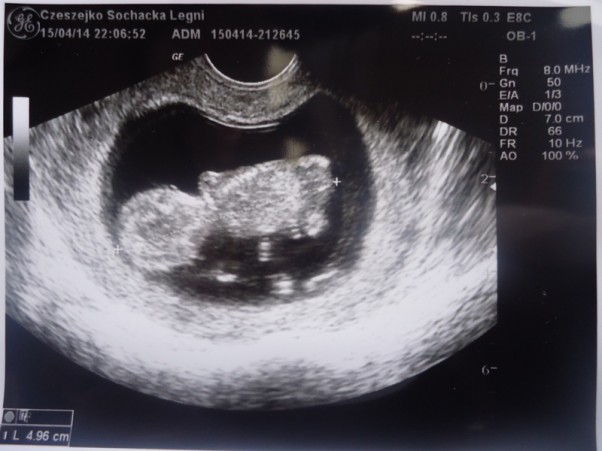

Druga wizyta u lekarza. Tym razem towarzyszył mi mój mąż. Nasz dzidziuś nie był już tylko maleńką kropeczką, po części wyglądał już jak mały człowieczek:) Miał już prawie 5cm.